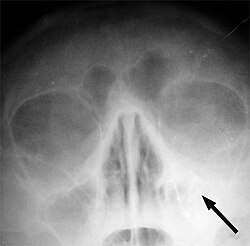

Sinusitis je upala paranazalnih sinusa čiji uzrok mogu biti bakterije, virusi, gljivice, alergije ili autoimune bolesti. Upala može zahvatiti bilo koji od paranazalnih sinusa. Prema trajanju razlikujemo akutne upale (tijek kraći od 4 tjedna), subakutne upale (tijek od 4 do 12 tjedana) i kronične upale (tijek duži od 12 tjedana).